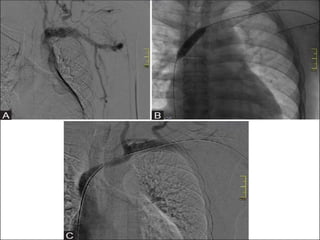

SOME EXAMPLES

APEX dialysis cme.pptx